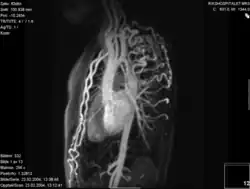

- Die Magnetresonanztomografie (=Kernspintomografie, MRT, NMR) ermöglicht eine gute Darstellung der ISTA. Durch die Flussmessungen ist eine Gradientenabschätzung möglich und gleichfalls eine 3-D-Rekonstruktion durchführbar.

Koarktation der Aorta mit verschiedenen bildgebenden Verfahren:

D – MR 3D-kontrastverstärktes Angiogramm mit großem Pseudoaneurysma (Pfeilspitze) nach vorheriger plastischer Operation Angioplastie. Auf der Rückseite ist echtes Licht zu sehen (Pfeil)[11]